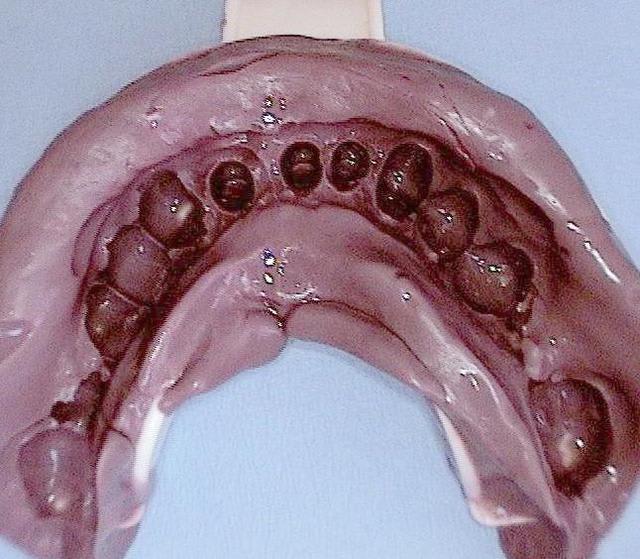

Sur le cas posté au début la dernière radio est après deux ans post OP. Ci dessous un autre exemple.

Les 12 premières photos sont un même cas avec implantation immédiate.

Le deuxième cas c est les photos 13 14 15 , (la photo 14 et 15 est après 5 ans)

Le dernier cas (3 dernieres photos), a été realisé il y a 5 ans il n y a pas de problème, je ne trouve pas les radios malheureusement je vais chercher encore un peu dans la journée.

Sur la photo 14 (implants mandibulaires)

Quelle est la longueur des implants ?

J'aime bien ce cas, sauf peut-être pour une certaine proximité des implants, car même si l'os peux être ok, pas facile pour la prothèse et son entretient.

ton commentaire m a fait remarqué que je n´ ai pas mis la photo de la prothèse du cas! merci ! :-)

ci dessous

cordialement

C'est certain que 10 ancrages (8 implants et 2 dents) c'est suffisant contre un complet amovible ;-)

Quelle est l'utilité des implant de 20 et 22 mm ?